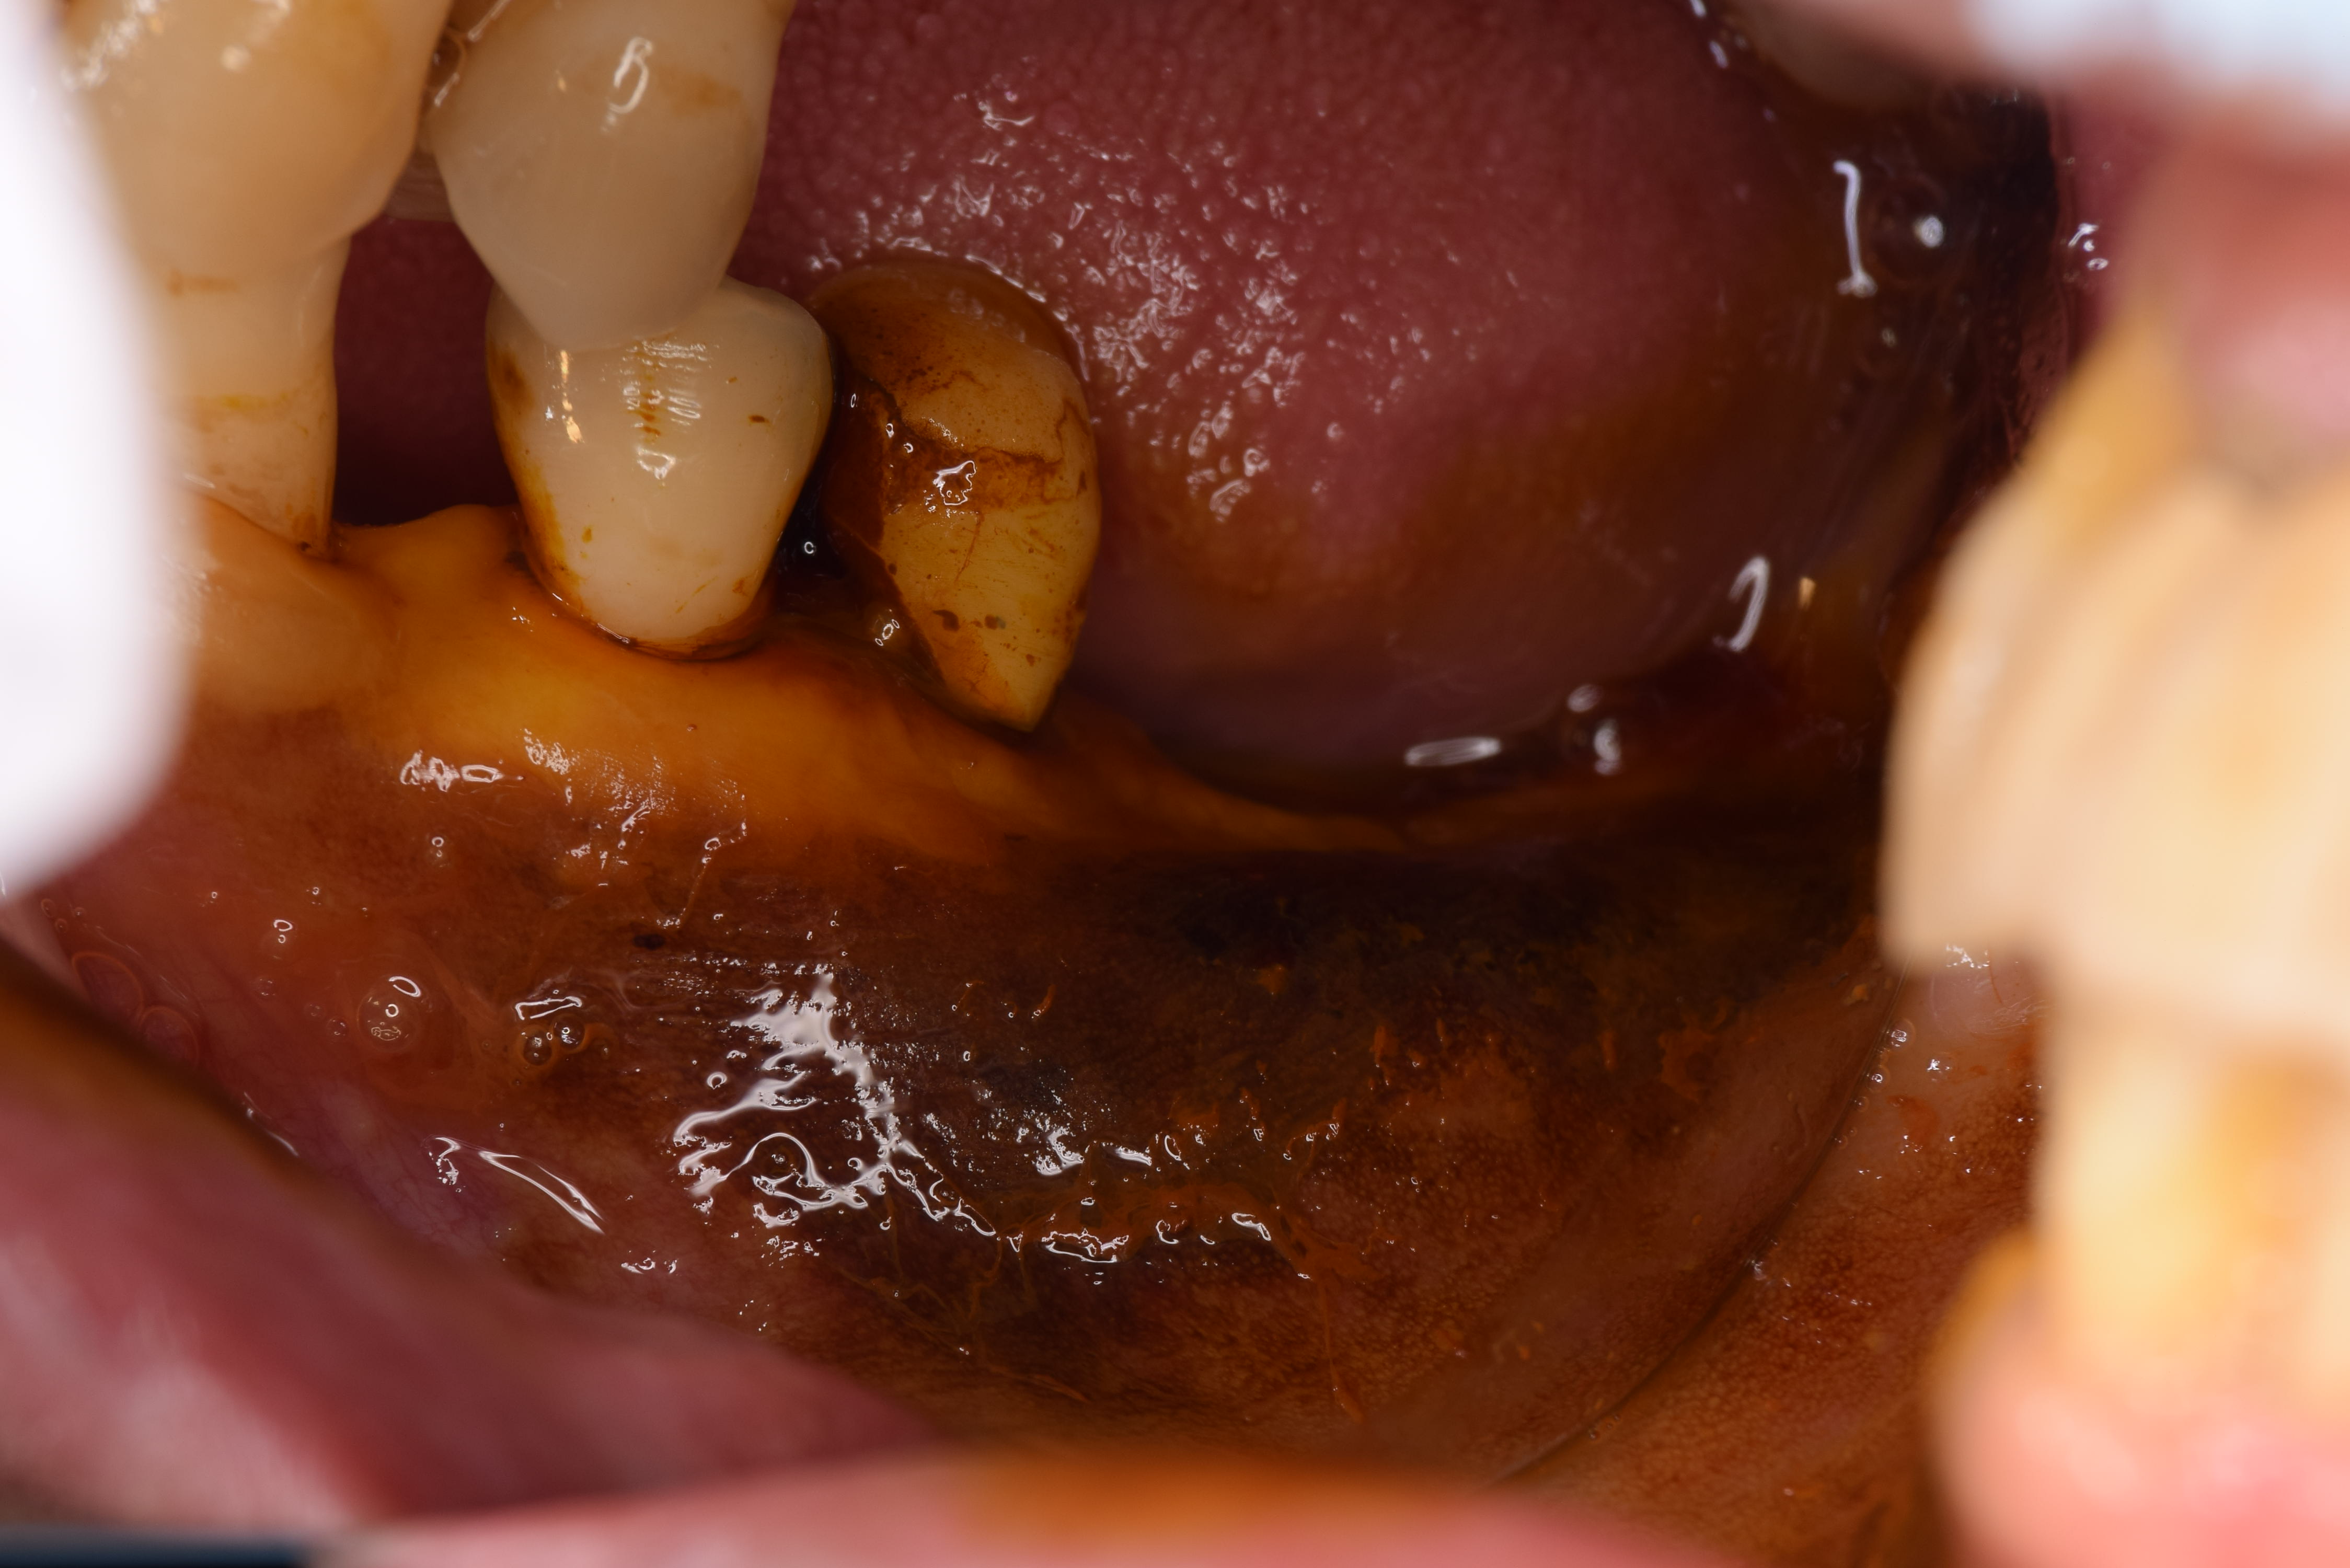

術前の状態です。(ミラー像)これをヨードで染めると角化粘膜と非角化粘膜の状態がわかります。

ヨードで染めた状態です。(ミラー像)濃く染まっている部分が非角化粘膜で弱い粘膜になります。あまり染まっていない部分が角化粘膜で強い粘膜になるのですが、インプラントまでの距離が1mm程度しかありません。

この状態でインプラントを入れてしまうと角化粘膜の不足による不具合が起こる可能性が出てきます。